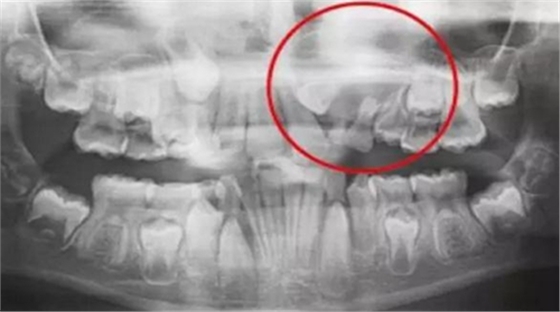

一名 23 區(qū)的9歲患者,在診所接受檢查時(shí)發(fā)現(xiàn)口內(nèi)中存在大范圍含牙囊腫[圖1]。由于上頜竇下沿出現(xiàn)大范圍突出,迫切需要接受囊腫去除手術(shù)[圖2和3]。

術(shù)前全景片[圖1]